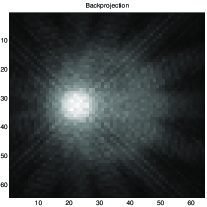

Fig. 8 shows results obtained in X-ray tomography image reconstruction. In this figure a) shows the original image, b) shows the projections (data), c) shows the backprojection reconstruction, d) shows a reconstruction using a Gaussian prior, e) shows a reconstruction using a Gamma prior, and f) shows a reconstruction using GNC with truncated quadratic regularization.

|

|

|

| a | c | e |

|

|

|

| b | d | f |

a) original, b) projections (data), c) Backprojection, d) Gaussian reconstruction, d) Gamma prior reconstruction, and e) GNC reconstruction